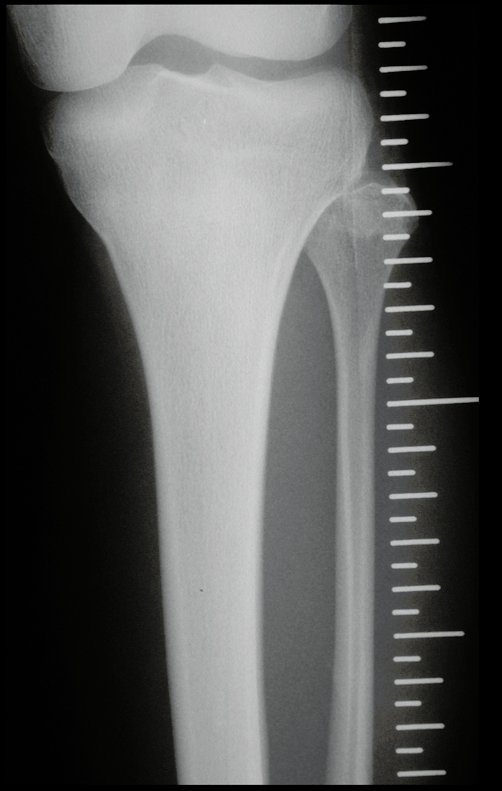

Tumor de células gigantes do rádio: Paciente feminina, 26 anos de idade, com dor no punho esquerdo havia dois meses. Procurou atendimento inicial em janeiro do ano 2000, quando foram feitas radiografias e tomografia, apresentando as seguintes imagens (Figuras 1 a 6).

Em maio de 2005, com a suspeita de tumor de células gigantes, foi encaminhada para um segundo hospital, cinco meses do primeiro atendimento. Novo encaminhamento foi feito, agora para nosso atendimento, em outubro daquele ano (Figuras 7 à 10).